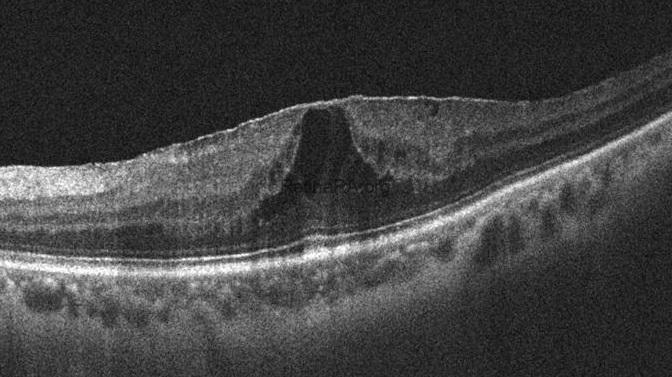

A 54-year-old female patient whose left vision has decreased for the last 6 months. Visual acuity is 20/40 in the left eye. Anterior segment examination was unremarkable. OCT revealed an ERM-Foveoschisis. The ERM-Foveoschisis, earlier referred to as the lamellar macular hole (LMH) or tractional LMH, was classified as a distinct entity apart from the LMH. In contrast to the LMH, the neurosensory tissue loss is not a diagnostic feature in ERM-Foveoschisis. OCT also revealed a free edge of ERM and RNFL (white arrow).

One month after surgery, foveoschisis disappeared, and a complete foveal depression occurred. The patient’s visual acuity had improved to 20/20.